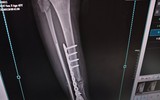

患者在沭阳铭和医院术后四月钢板断裂 院方称未遵医嘱所致 家属否认并质疑诊疗